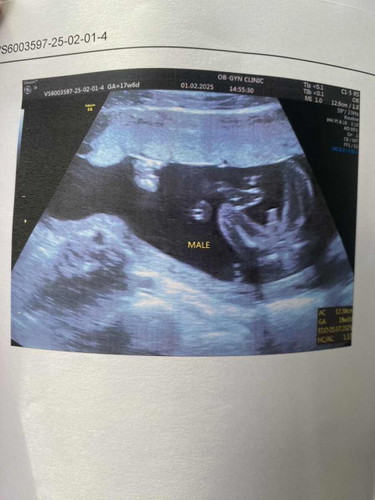

รบกวนขอสอบถามค่ะ ว่าแบบนี้ใช่ชาย 100%ไหมคะ ไม่ใช่สายสะดือใช่มั้ยคะ 🥺

เหมือนของบ้านนี้เลยค่ะ หมอบอกผู้ชาย👶🏻